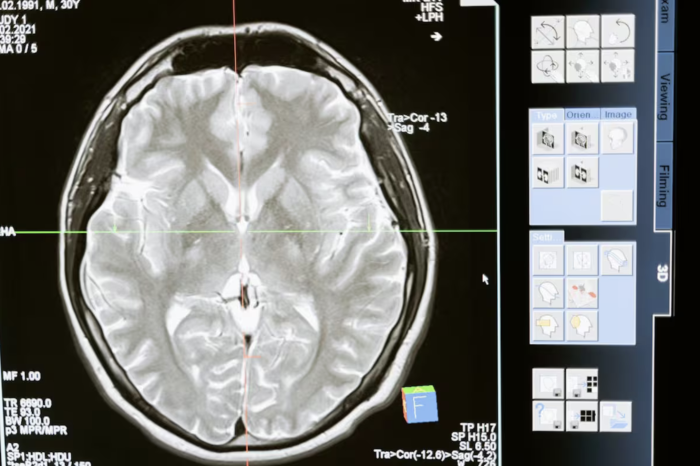

Un estudio realizado por investigadores en Francia evidenció una relación directa entre el hambre, los niveles de glucosa en sangre y la capacidad del cerebro para almacenar recuerdos. El hallazgo aporta nuevas pistas sobre por qué el rendimiento mental puede verse afectado cuando el cuerpo carece de energía.

De acuerdo con los científicos, la glucosa no solo funciona como fuente de energía, sino que desempeña un papel fundamental en la formación de la memoria a largo plazo. Cuando sus niveles son adecuados, el cerebro puede consolidar mejor la información; sin embargo, esta función se debilita cuando el organismo está en ayuno o con baja disponibilidad de azúcar.

El estudio explica que, en condiciones de hambre, el cerebro prioriza funciones básicas de supervivencia, reduciendo los recursos destinados a procesos cognitivos complejos. Esto provoca que algunos recuerdos no se fijen correctamente o resulten más difíciles de recuperar posteriormente.

Además, se encontró que la glucosa influye en la comunicación entre neuronas, facilitando la creación de conexiones necesarias para almacenar información. Cuando este suministro es insuficiente, dichos procesos se vuelven menos eficientes, lo que puede derivar en olvidos o fallas momentáneas en la memoria.